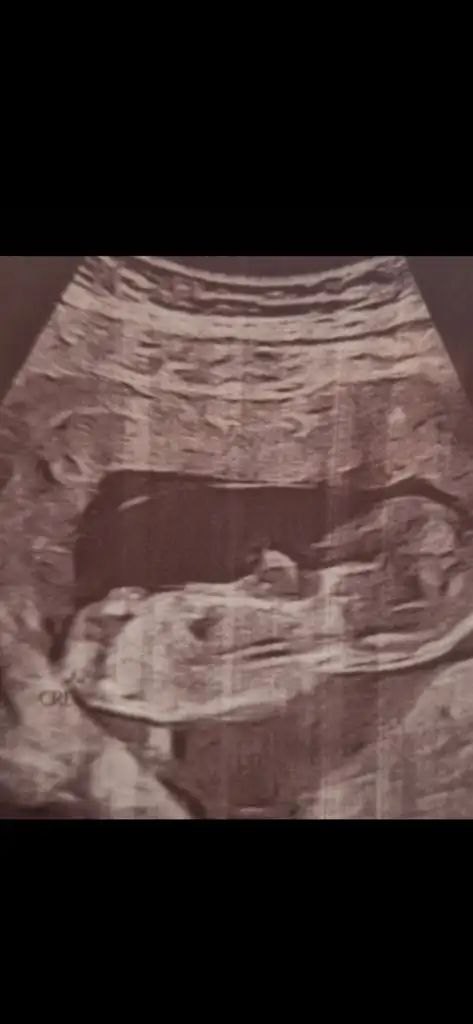

Bence net kızBanada bakın yaaa![]()

Nerden belli oluyorBence net kız![]()

Teşekkür ederim canımBence net kız![]()